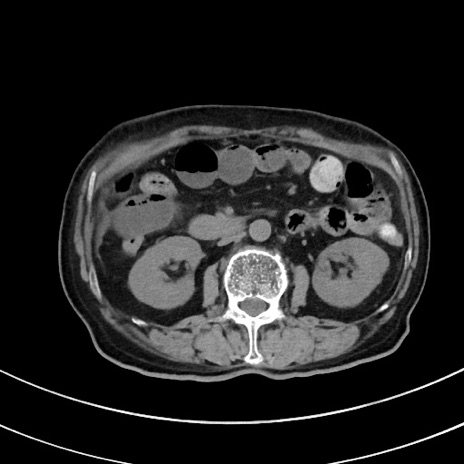

症例33(横断像)

【症例】70歳代 女性

【主訴】心窩部痛

【現病歴】延髄病変の精査・加療にて神経内科入院中。本日より心窩部痛あり。

【既往歴】虫垂炎

【身体所見】右下腹部を中心に圧痛と反跳痛あり。

【データ】WBC 10900、CRP 0.02